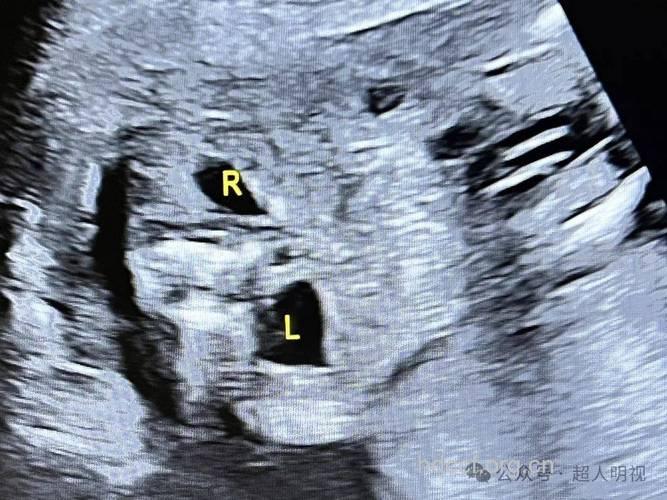

胎儿肾积水大多属于正常现象

专家介绍,在怀孕17—18周之后,通过B超检查,能够检查出胎儿是否患有肾积水。就临床调查发现,有大约5‰的胎儿会出现肾积水的情况,但是只要经过确切的诊断与治疗,这种情况是十分乐观的。

一般来说,绝大部分胎儿肾积水会随着发育成长自动恢复正常,只有少部分重度肾积水胎儿需要出生后手术治疗。很多宝宝在检查时都会出现肾积水的情况,但是产后出现肾积水胎儿的几率不是很高,即使出现治愈率也是很高的。